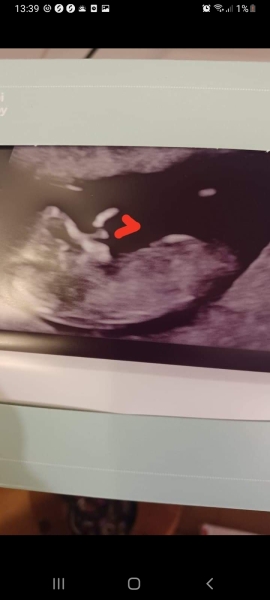

What is everyone's guess on my scan please? Be interesting to know as Ive no clue ( Though Ive 2x of each already!)

(The red mark Indicates an arm - Though looks like an extended nose- I was showing my eldest DC!)